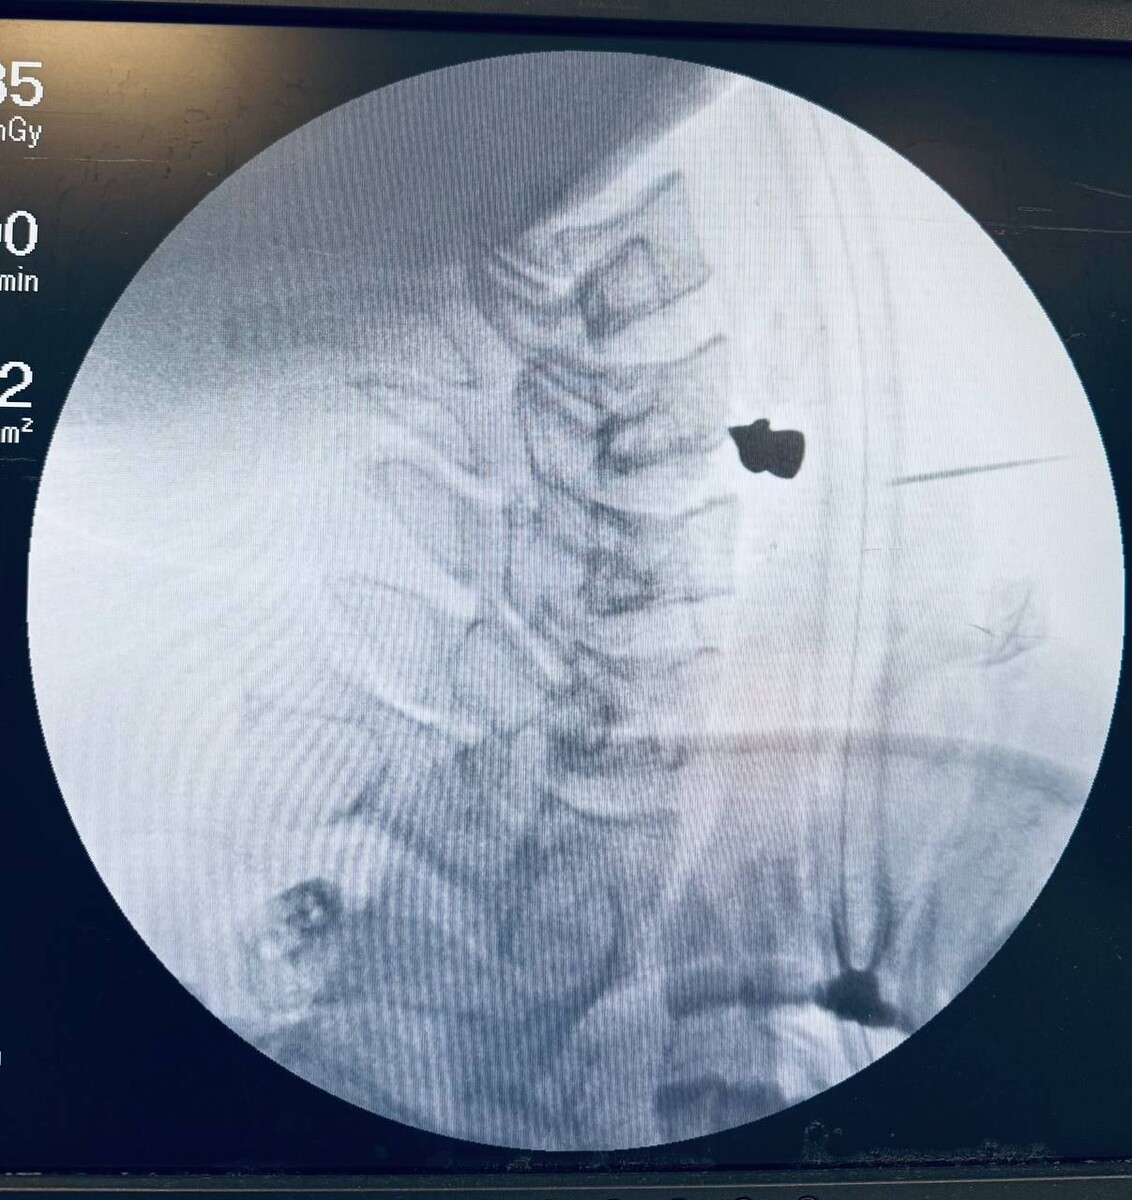

В Татарстане 25-летнему жителю Зеленодольского района удалили пулю из шеи после неосторожного обращения с пневматическим ружьём. Молодой человек случайно выстрелил в себя во время разборки оружия. Как рассказал пострадавший, он не заметил, как сработал механизм, и лишь почувствовал, как из шеи хлынула кровь. Друзья сразу доставили его в центральную районную больницу, откуда пациента перевели в Республиканскую клиническую больницу Казани. Обследование показало, что пуля чудом не задела жизненно важные органы — артерию, трахею и пищевод, но остановилась в позвоночнике. Мужчина испытывал трудности с глотанием и речью. Операцию по извлечению пули провели заведующий ЛОР-отделением Марат Гилялов и заведующий отделением нейрохирургии Георгий Майков. Хирурги справились всего за 20 минут, после чего наложили швы на рану. Сейчас пациент находится в палате и проходит восстановление. Фото: РКБ

Обследование показало, что пуля чудом не задела жизненно важные органы — артерию, трахею и пищевод, но остановилась в позвоночнике. Мужчина испытывал трудности с глотанием и речью.

Операцию по извлечению пули провели заведующий ЛОР-отделением Марат Гилялов и заведующий отделением нейрохирургии Георгий Майков. Хирурги справились всего за 20 минут, после чего наложили швы на рану.